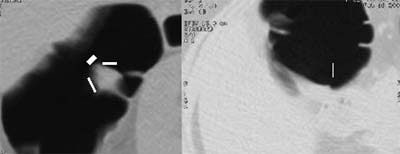

![]() |

| Left to right: prone and supine axial images of a flat tubular adenoma along the fold of the hepatic flexure. The lesion was missed by both radiologists, but detected by CAD (represented by lines in image at left). From Fletcher JG, Summers RM, Johnson CD, MacCarty RL, Wilson LA. Lessons in Detection: Contribution of Computer-aided Detection with Perceptively Challenging Lesions at CT Colonography. Supplement to Radiology November 2002, Vol. 225, p. 304. RSNA December 1-6, 2002, Chicago. Image courtesy of Dr. Joel Fletcher, © Mayo Medical Foundation, 2002. |